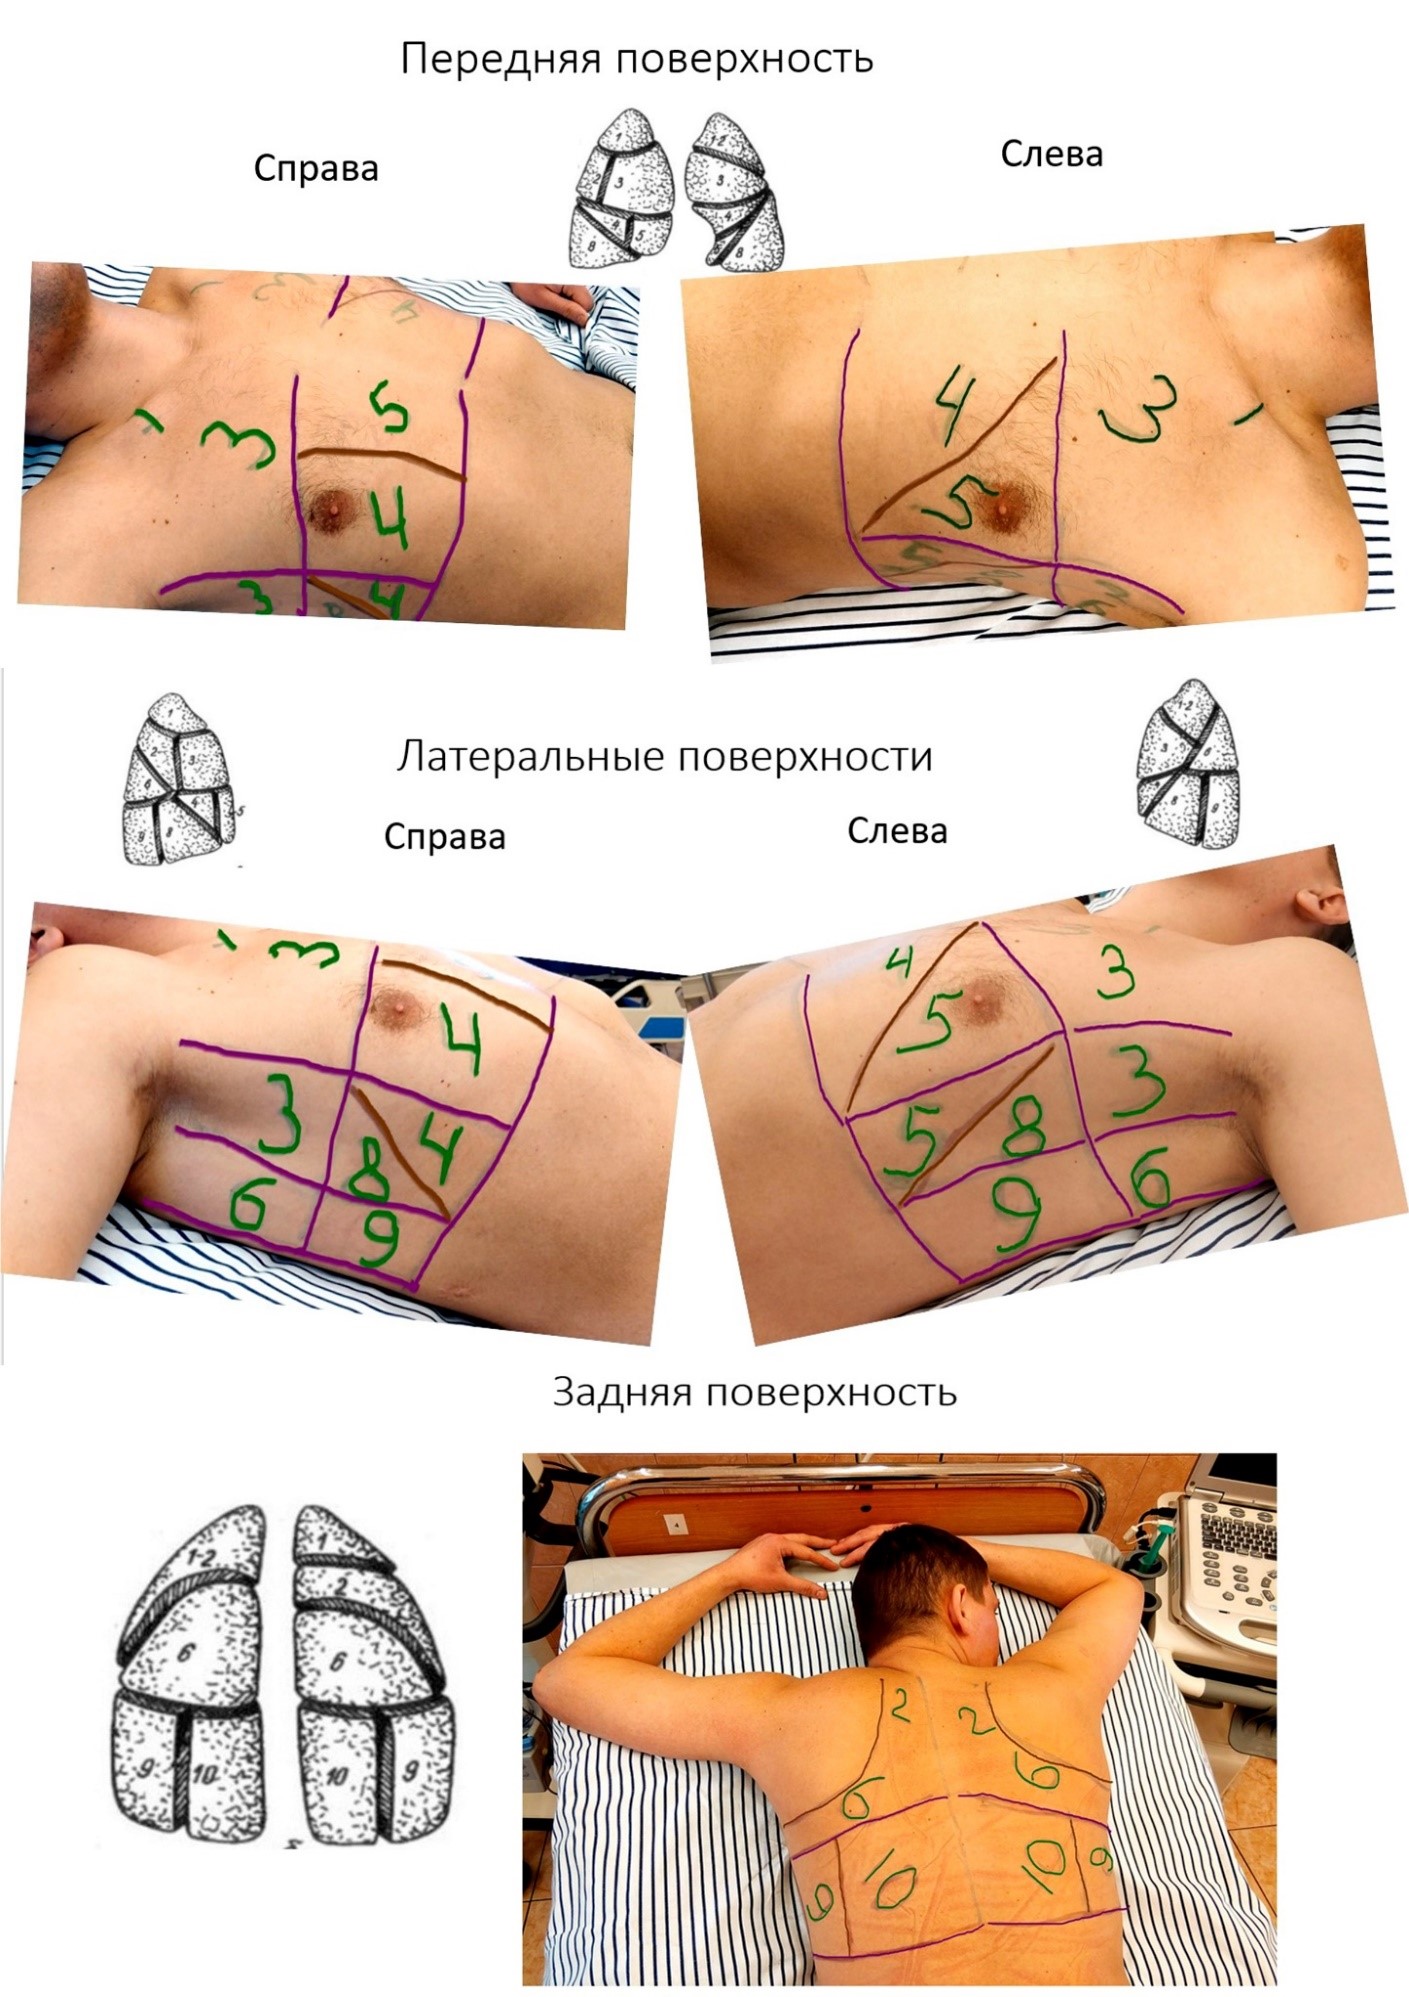

Анатомические изображения сегментов легких различных животных

Раздел: Другие животные